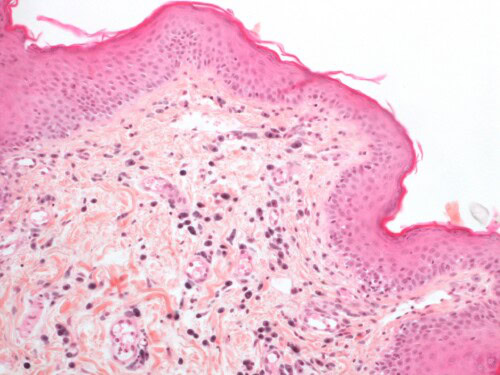

L’examen histopathologique met en évidence une dermatite périvasculaire marquée, focalement pustuleuse. L’infiltrat dermique est riche en granulocytes neutrophiles, éosinophiles et en mastocytes.

Photo 16 : Examen histopathologique cutané (coloration HES) :

notez l’infiltration dermique par de nombreux mastocytes

Photo 17 : Examen histopathologique cutané (coloration HES) :

pustule neutrophilique intra-épidermique

La présence de granulocytes éosinophiles à la cytologie et à l’histopathologie et de mastocytes à l’histopathologie sont certes en faveur d’une hypersensibilité, mais absolument pas diagnostique d’un SCAF.

D’ailleurs l’examen histopathologique ne permet pas non plus le diagnostic d’une dermatite à Malassezia, notamment compte-tenu du processus utilisé qui fait disparaître partiellement la couche cornée et ne permet donc que rarement d’observer les levures. Pour Pickle, son intérêt a été d’écarter une alopécie paranéoplasique et une démodécie qui n’aurait pas été diagnostiquée par les raclages, souvent négatifs chez le chat.